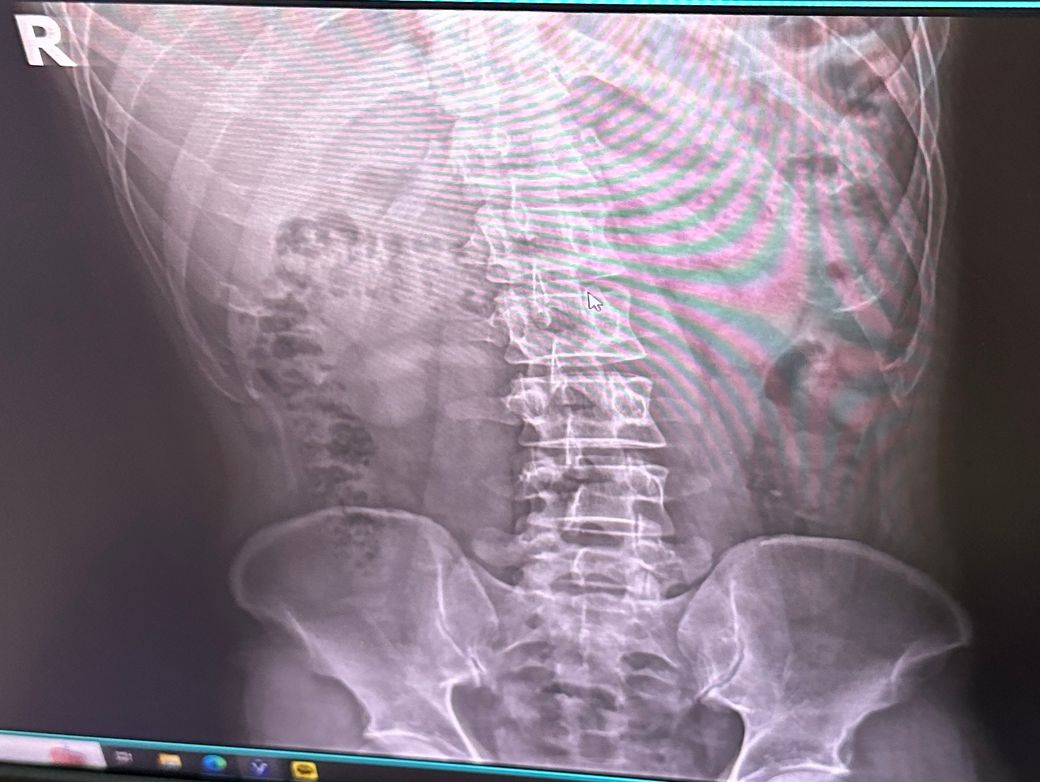

• 4번 째 사진

측만증이 다양한 원인이 있지만 엑스레이 상에서 보아도 측만증이 있어보이긴 합니다. 근데 측만증이라는게 선천적일수도 있고 후천적일 수도 있고 이에따라 치료법이 다르고.. 또한 내가 등이 아프면서 안아프게 하려고 몸을 꼬니까 측만증이 있는것처럼 보일 수 있습니다.

사진상으로 많은걸확인할수는없지만 지금가지고있는 측만증의경우 자세적인문제가있을수있는데요 잠을자거나 휴식을취할때 엎드리거나 만세를하고있는동작은 목어깨나 허리, 몸에 부담을줄수있기때문에 추천하지않습니다

측만증은 일반적으로 유전적 요인이나 오래된 잘못된 자세로 인해 발생할 수 있으며 급격한 통증이 나타나지 않으면 그 자체로 큰 문제가 되지 않는 경우도 많습니다. 신경 부종은 압박에 의해 발생할 수 있으며 잘못된 자세나 장시간 앉는 습관이 영향을 미칠 수 있습니다.